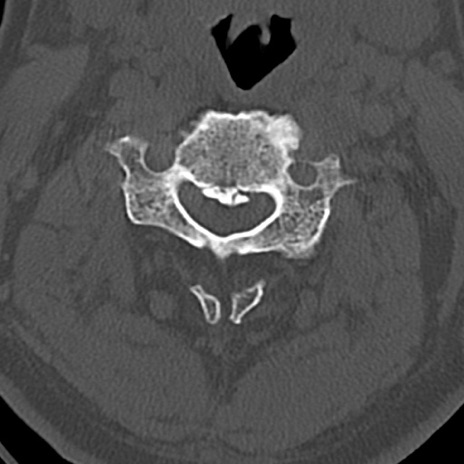

頚椎CT

横断像